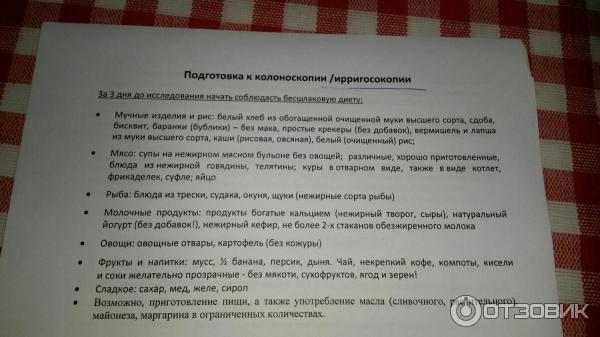

Подготовка к ирригоскопии: необходимые препараты